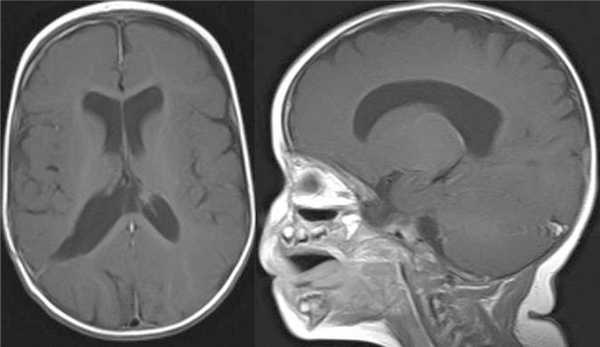

Девочка, 4 мес жизни. Ребенок от 2-й беременности, протекавшей без осложнений, роды в срок, родоразрешение посредством кесарева сечения. Первый ребенок из двойни. С рождения девочка была более сонлива, чем второй ребенок, что настораживало мать. Это явилось причиной проведения ультразвукового исследования (УЗИ) головного мозга в возрасте ребенка 3 нед. Обнаружено объемное образование в полости черепа, при МРТ подтвержден диагноз опухоли правого бокового желудочка (рис. 1, а).

Рисунок 1. МРТ с контрастным усилением в аксиальной (слева) и сагиттальной (справа) проекции: ПСС тела и переднего рога правого бокового желудочка. а — возраст ребенка 1 мес; б — возраст ребенка 2 мес: миграция ПСС в задний рог правого бокового желудочка; в — возраст ребенка 3 мес: миграция ПСС в тело и передний рог правого бокового желудочка.

Отсутствие клинической симптоматики, малый возраст ребенка послужили поводом для динамического наблюдения.

Контрольная МРТ головного мозга через 1 мес выявила миграцию опухоли в задний рог правого бокового желудочка, размер опухоли немного увеличился (см. рис. 1, б).

На контрольной МР-томограмме головного мозга выявлено значительное увеличение размеров опухоли и ее миграция в передний рог и тело бокового желудочка (см. рис. 1, в).

МРТ головного мозга с контрастным усилением показала радикальное удаление опухоли и отсутствие осложнений (рис. 6).

Рисунок 6. МРТ с контрастным усилением (аксиальный и сагиттальный срезы) — радикальное удаление опухоли. На аксиальном срезе виден узкий, фактически закрывшийся раневой ход. Признаков гидроцефалии и напряженных субдуральных скоплений нет.